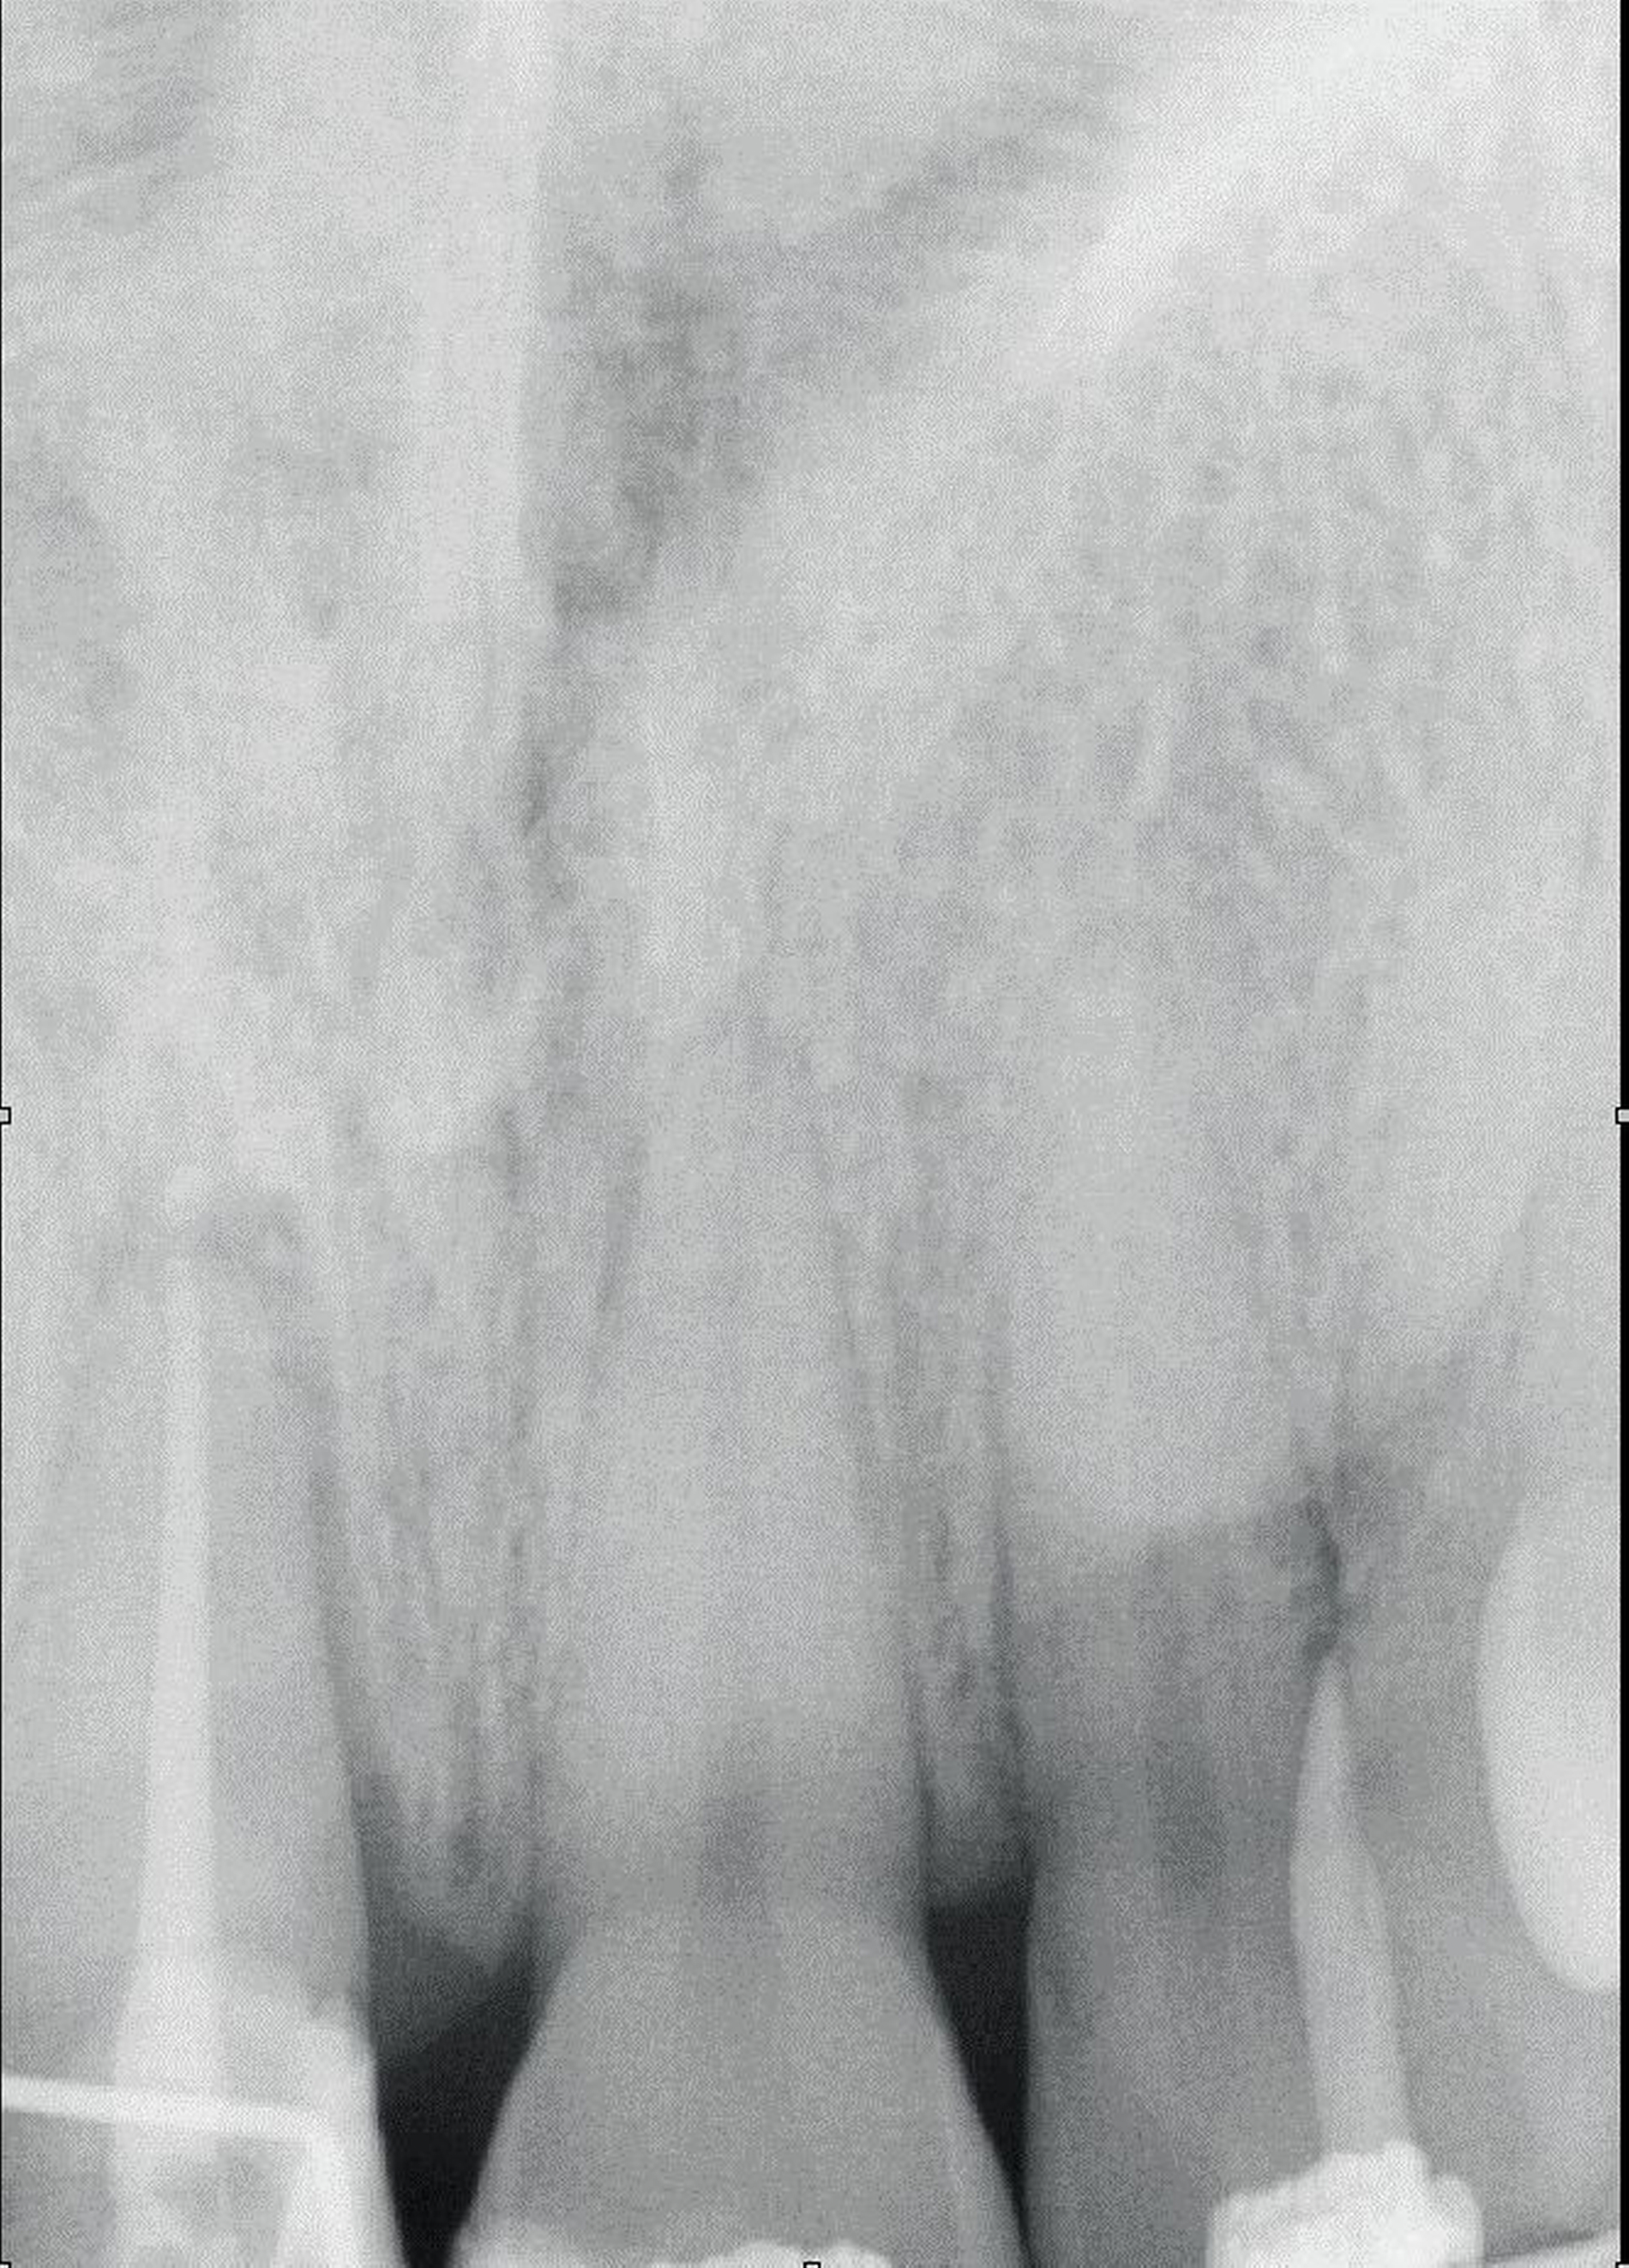

Ein 22-jähriger Patient stellte sich im Februar 2020 im zahnärztlichen Notdienst der Klinik für Zahn-, Mund- und Kieferkrankheiten Mainz vor. Aufgrund einer Synkope war er mit dem Oberkiefer auf den Rand einer Badewanne gestürzt. Intraoral zeigte sich der Zahn 12 mit einer Schmelz-Dentin-Fraktur ohne Pulpabeteiligung (unkomplizierte Kronenfraktur), der Zahn 11 mit einer Kronen-Wurzel-Fraktur mit Pulpabeteiligung und der Zahn 21 mit einer Schmelz-Dentin-Fraktur mit Pulpabeteiligung (komplizierte Kronenfraktur). Die Zähne zeigten keine erhöhten Lockerungsgrade oder Dislokationen (Abbildung 2). Herausfordernd für die weitere Versorgung war der Frakturverlauf an Zahn 11, an dem die Frakturkante palatinal tief subgingival und mesio-palatinal auch subkrestal lag. Röntgenologisch konnte die klinisch gestellte Verdachtsdiagnose bestätigt und eine Wurzelfraktur ausgeschlossen werden (Abbildung 3).